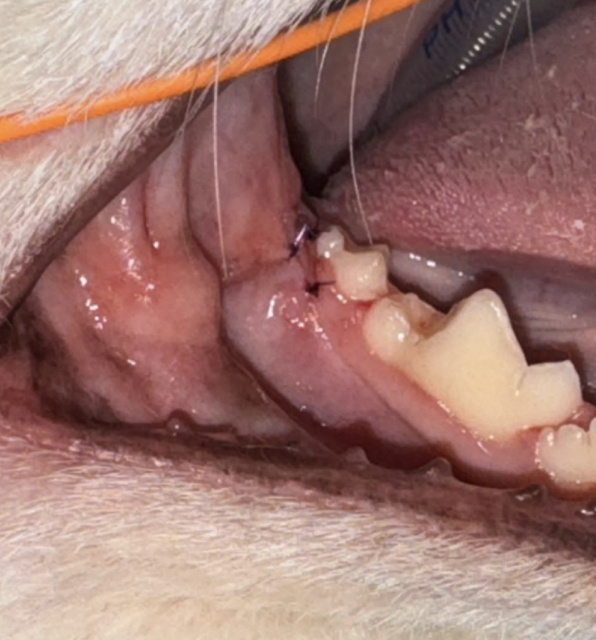

・After

専門の器具を使い、歯の表面や歯周ポケットの歯石をきれいに取り除く処置「スケーリング」を行いました。

その後、歯の表面をなめらかに磨いて仕上げました。これは歯の表面の細かい傷をなめらかにすることで、歯石が付きやすくなるのを防ぐために行います。

▲ 埋伏歯 抜歯後

▲ 抜歯後に歯肉縫合

埋伏歯は抜歯を行い、歯肉は縫合を行いました。

縫合の糸は、髪の毛よりも細い糸を使用しております。また、縫合糸は数ヶ月で溶ける糸を使用するため、基本的には抜糸の必要がありません。